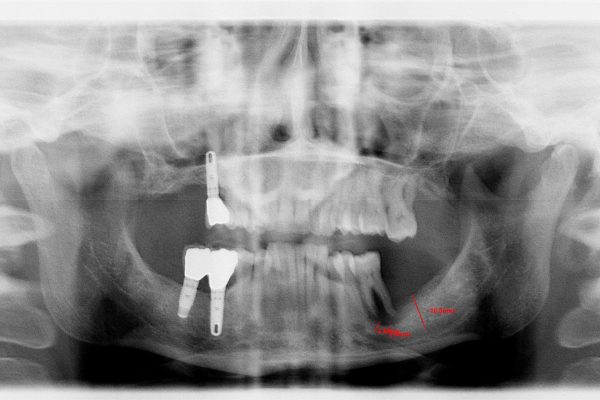

Il caso Clinico:

Importante perdita ossea Verticale ed orizzontale provocata dalla perdita di Impianti posizionati a causa della MANCANZA di una attenta diagnosi, piano di trattamento e capacità operativa, che avrebbero mostrato l’impossibilita di posizionare gli Impianti senza ripristinare lo spessore osseo adeguato …